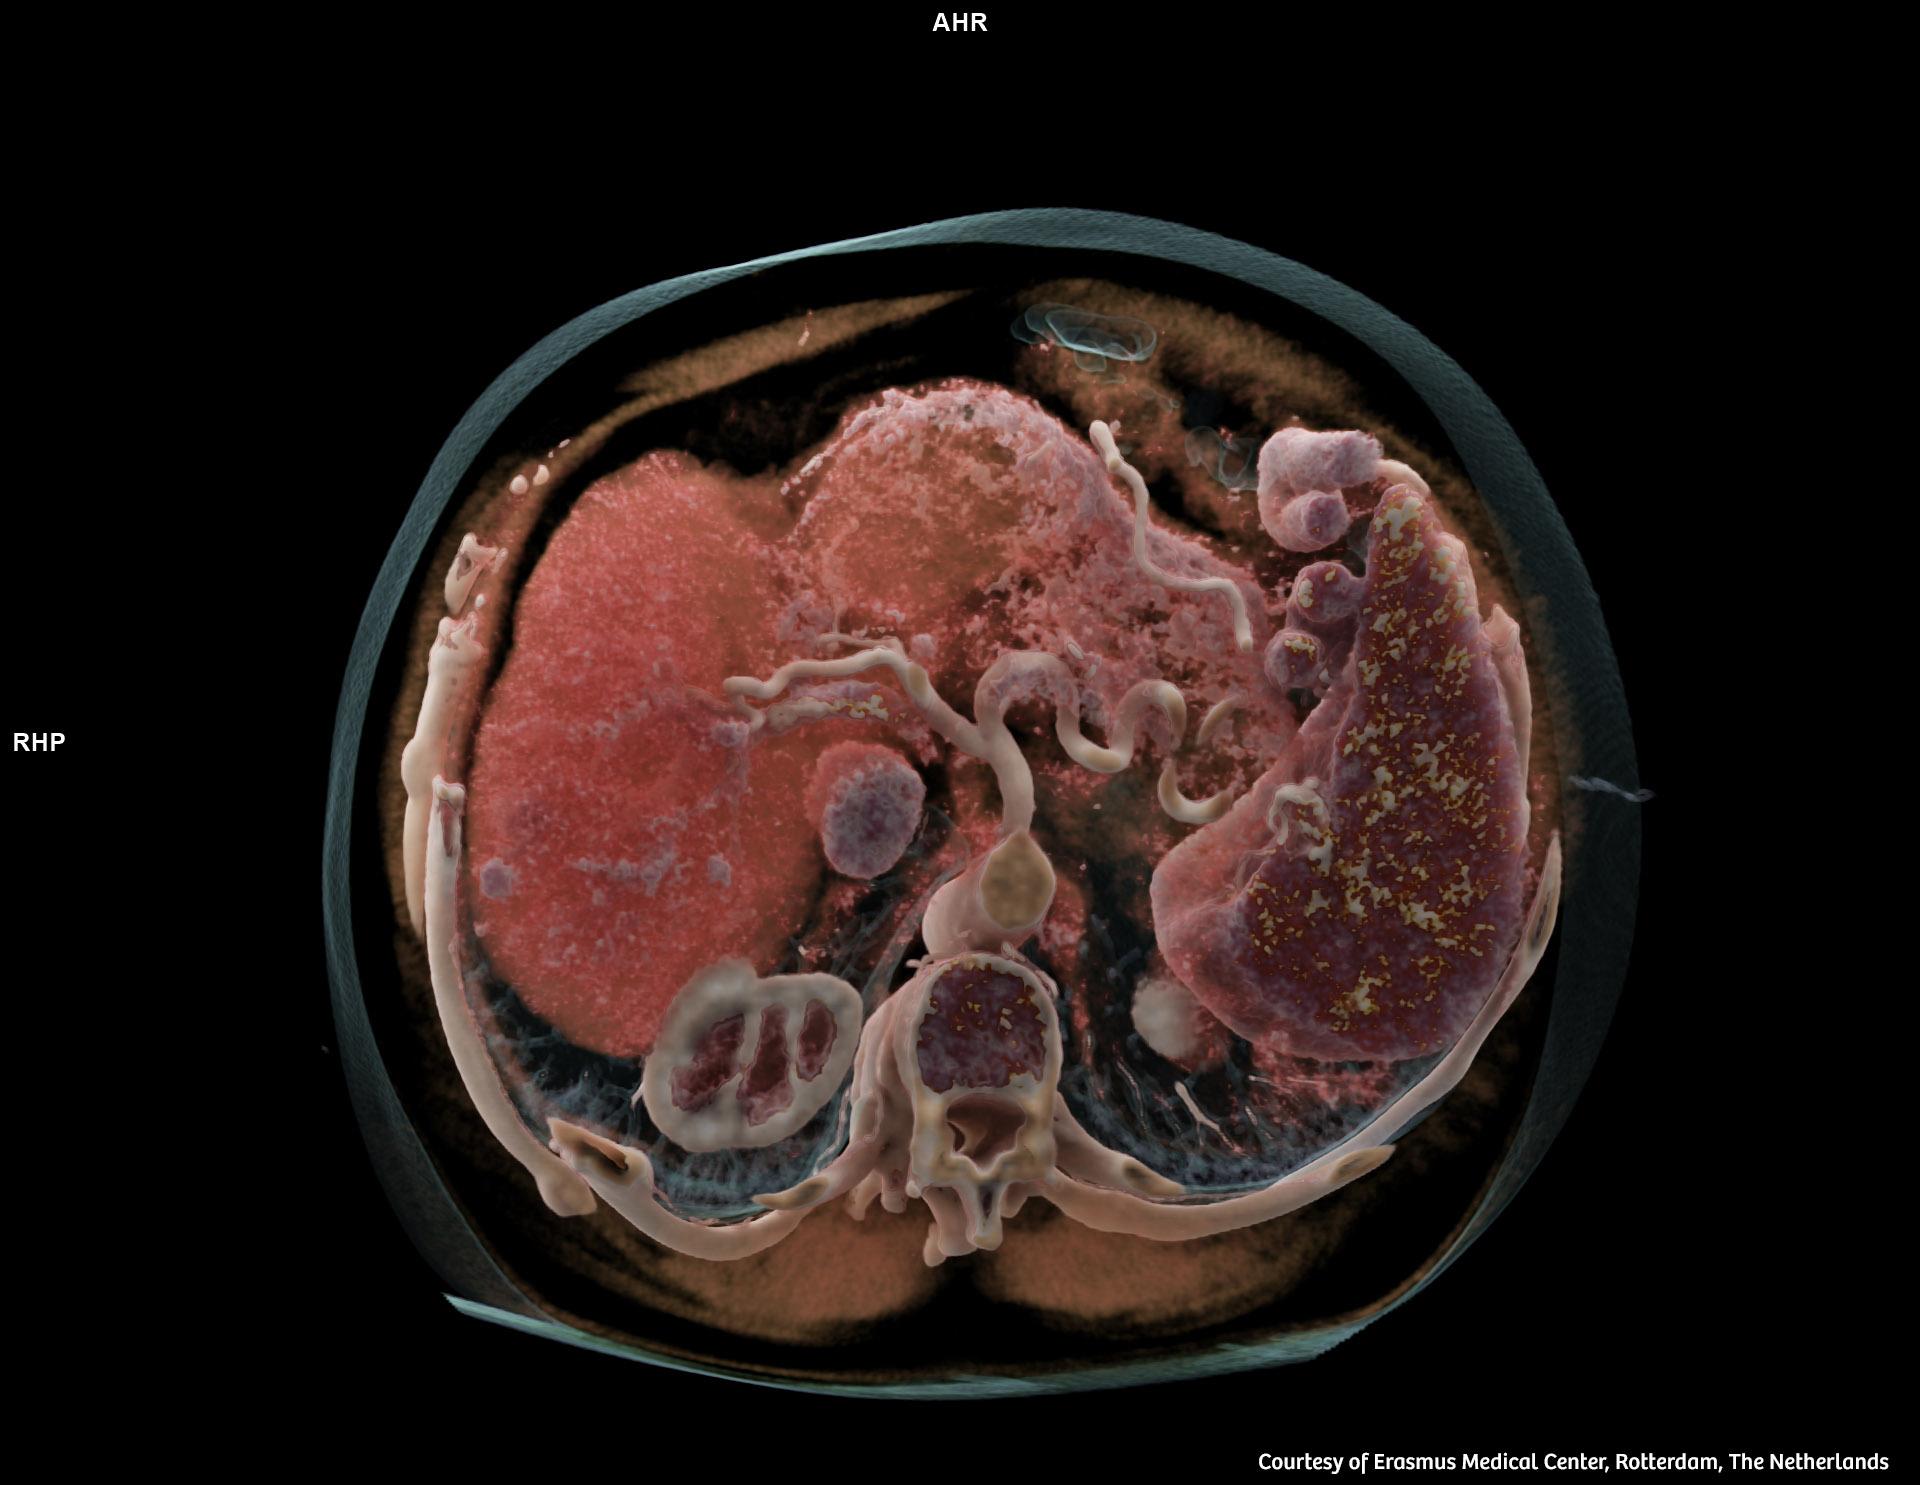

Я как раз вижу совсем другое. Да, приход конкурентов извне - блокируется. Но он блокируется вовсе не деньгами, а контролем за технологиями. А внутри системы я никакого почивания на лаврах не вижу, наоборот - дикая совершенно гонка, конкуренция и ускорение всего, что только можно. В моей профессиональной области, например, наконец-то вызрели photon counting CT. Их массовое применение произведёт революцию в неинвазивных методах исследования, но кроме того, потянет за собой туеву хучу смежных отраслей и технологий. Если даже поверхностно, это УЖЕ сродни фантастике. Что там получится за 10-15 лет развития, не поддаётся даже воображению.

Я как раз вижу совсем другое. Да, приход конкурентов извне - блокируется. Но он блокируется вовсе не деньгами, а контролем за технологиями. А внутри системы я никакого почивания на лаврах не вижу, наоборот - дикая совершенно гонка, конкуренция и ускорение всего, что только можно. В моей профессиональной области, например, наконец-то вызрели photon counting CT. Их массовое применение произведёт революцию в неинвазивных методах исследования, но кроме того, потянет за собой туеву хучу смежных отраслей и технологий. Если даже поверхностно, это УЖЕ сродни фантастике. Что там получится за 10-15 лет развития, не поддаётся даже воображению.

Tico> В моей профессиональной области, например, наконец-то вызрели photon counting CT. Их массовое применение произведёт революцию в неинвазивных методах исследования, но кроме того, потянет за собой туеву хучу смежных отраслей и технологий. Если даже поверхностно, это УЖЕ сродни фантастике. Что там получится за 10-15 лет развития, не поддаётся даже воображению.

Tico> В моей профессиональной области, например, наконец-то вызрели photon counting CT. Их массовое применение произведёт революцию в неинвазивных методах исследования, но кроме того, потянет за собой туеву хучу смежных отраслей и технологий. Если даже поверхностно, это УЖЕ сродни фантастике. Что там получится за 10-15 лет развития, не поддаётся даже воображению.